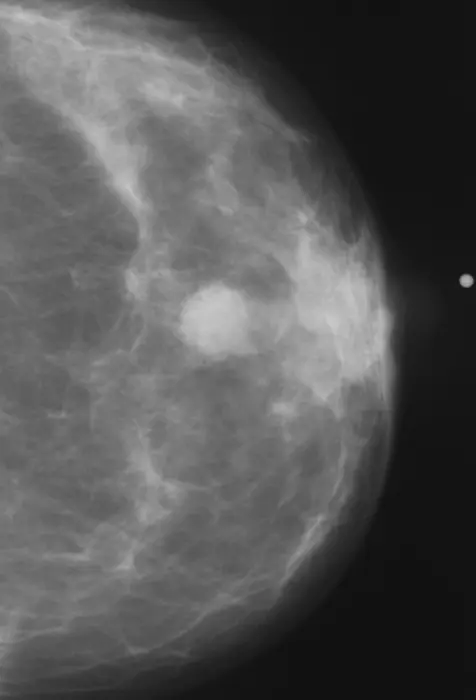

Abnormal Mammogram

IMAGE:

ABNORMAL MAMMOGRAM.

CREDIT: RSNA

CHICAGO – A deep learning artificial intelligence (AI) model that was developed using only mammogram image biomarkers accurately predicted both ductal carcinoma in situ (DCIS) and invasive carcinoma, according to research being presented today at the annual meeting of the Radiological Society of North America (RSNA). Additionally, the model showed no bias across multiple races.